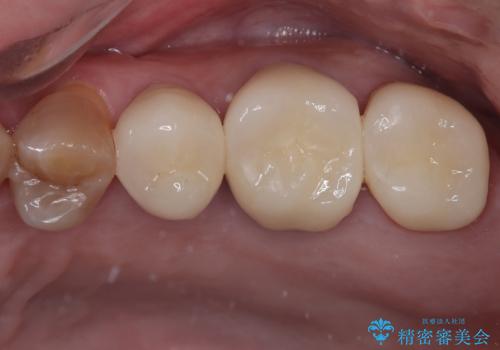

下顎大臼歯の再根管治療とオールセラミッククラウンによる補綴治療

奥歯がうずく